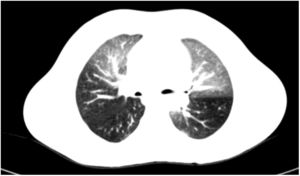

He consulted due to a febrile episode lasting 48h, with sparsely productive cough as the only symptom. On examination, he showed good general status, asthenia, mild tachypnea, and fine crackles in the right lung base. Clinical laboratory tests showed C-reactive protein 220mg/l and procalcitonin 7.4ng/ml, deteriorating creatinine clearance and worsening of baseline pancytopenia. Chest radiograph was normal. With sepsis of gastrointestinal origin as an initial diagnosis, treatment began with meropenem; the patient became afebrile 24h later and his infection parameters improved. Urinary, gastrointestinal, and ENT infectious foci and pneumonia were ruled out. Despite clinical improvement, bilateral pulmonary and migratory crackles persisted, with normal oxygen saturation at all times, so during the week that he was hospitalized, the following tests were conducted: pulmonary ventilation–perfusion scintigraphy, normal; spirometry, mixed pattern; diffusing capacity of the lung for carbon monoxide, lower limit of normal; and finally high-resolution CT (HRCT) that confirmed the suspected diagnosis of BO (Fig. 1, mosaic attenuation pattern).

BO is a clinical syndrome characterized by chronic and irreversible airflow obstruction caused by inflammatory changes associated with fibrosis in the small airway.2,5 The most common etiologies in children are immunosuppression and postinfective syndromes.1,4 The clinical picture in most patients is very nonspecific, so the initial diagnostic approach is difficult.4,5 Before BO is suspected, spirometry must show a fixed obstructive pattern and the characteristic mosaic attenuation pattern (areas of air trapping and atelectasis, and bronchial dilation) must be observed on HRCT (inspiration and expiration). Biopsy is usually not required if HRCT is available.5 The initial treatment consists of combined therapy with inhaled glucocorticoids, macrolides, and beta-2 adrenergic bronchodilators.3 When the disease is established, this treatment is supportive and must include immunosuppressive drugs. Lung transplantation is indicated in patients who have progressed.1